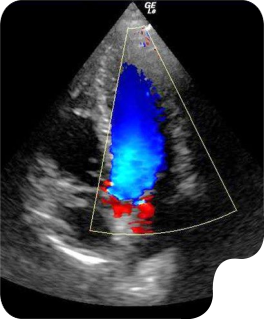

Hands-on ultrasound training for students and professionals. Bridging the gap between learning and real-world practice.